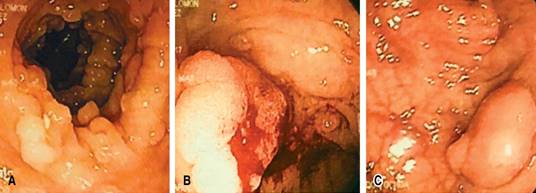

Se trata de un hombre de 56 años de edad, bajo tratamiento médico por hipertensión arterial de larga evolución y cardiopatía isquémica tratada con colocación de stent coronario hace dos años, antecedente heredofamiliar de cáncer de colon en dos familiares de primer grado menores de 50 años. Acude a valoración externa por historia de tres meses de evolución con sangrado de tubo digestivo bajo (STDB) acompañado de síndrome anémico, se realiza colonoscopia observando poliposis múltiple (más de 200 pólipos), con lesiones de aspecto neoplásico en colon sigmoides y colon transverso (Figura 1). No se encontraron lesiones cutáneas u óseas anormales ni tampoco se identificó la presencia de hipertrofia del pigmento del epitelio retiniano.

Figura 1: Colonoscopia donde se observa poliposis múltiple (A), con lesiones de aspecto neoplásico en colon transverso (B) y colon sigmoides (C).